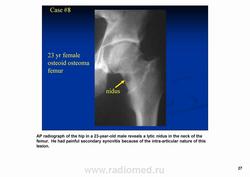

Остеоидная остема.

Диагностика и дифференциальная диагностика.